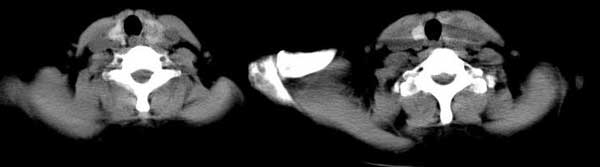

女 48岁 无意中发现左侧颈部肿块

图片太小,好象双侧都有,肿瘤双侧还是少见,支持甲状腺肿(囊变)

左侧甲状腺下极可见类圆形结节样低密度病灶,边缘清晰,未见明显周围组织受侵,颈部未见明确淋巴结肿大;右侧甲状腺形态密度未见异常。

诊断意见:左侧甲状腺结节样病灶,多考虑甲状腺腺瘤。建议ect检查。

见双侧结节,边清。1甲状腺肿,2腺瘤。

双侧甲状腺弥漫性密度减低,左侧可见低密度结节边界清晰,周围软组织未见异常,考虑双侧结节性甲状腺肿